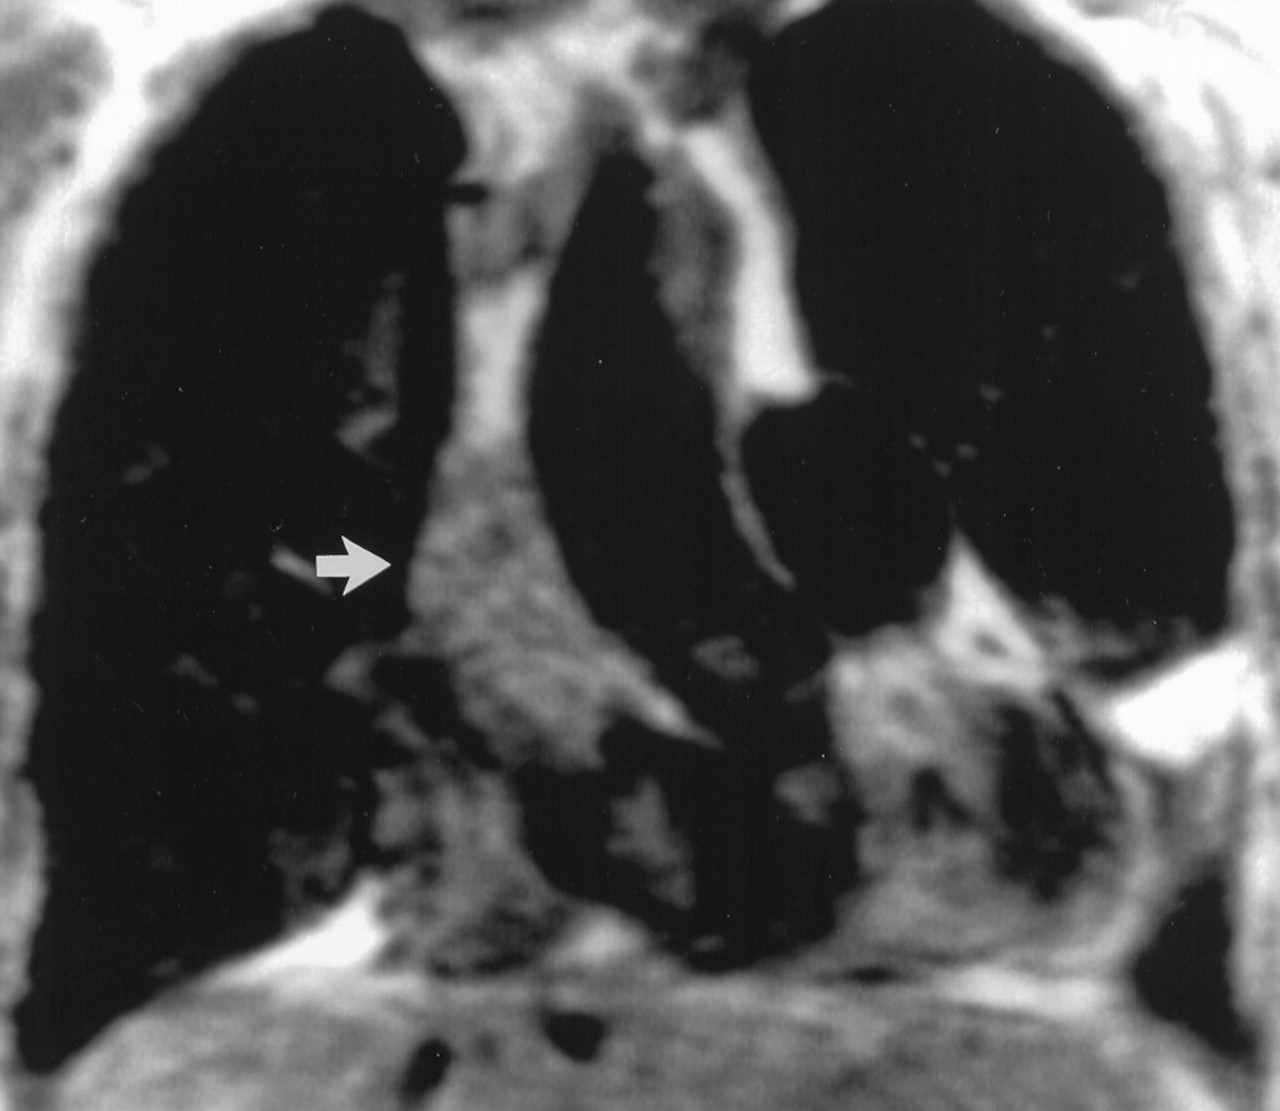

Ангиосаркома

Ангиосаркома - наиболее частая разновидность, составляющая 33% первичных злокачественных опухолей. У мужчин встречается в 2- 3 раза чаще, чем у женщин. Опухоль может поражать любые отделы сердца, наиболее часто - правое предсердие.

Ангиосаркома макроскопически представляет собой плотное бугристое образование, инфильтрирующее ткани. На разрезе видны очаги некроза и кровооизлияний. Микроскопически определяются веретенообразные, полигональные или округлые клетки, образующие синцитий и складывающиеся в беспорядочно расположенные тяжи. Характерным является образование различных по размерам и форме сосудистых полостей, заполненных кровью и сообщающихся между собой. Между клетками опухоли находятся рыхлые сети аргирофильных волокон, напоминающих базальную мембрану.